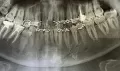

Прикрепленые фото

• Исходя из данного снимка, теоретически шины можно снимать, но неизвестна исходная картина, вид перелома и как быстро была оказана первая помощь. После снятия шин, ускорить восстановление функции челюсти поможет механотерапия, лечебная физкультура.